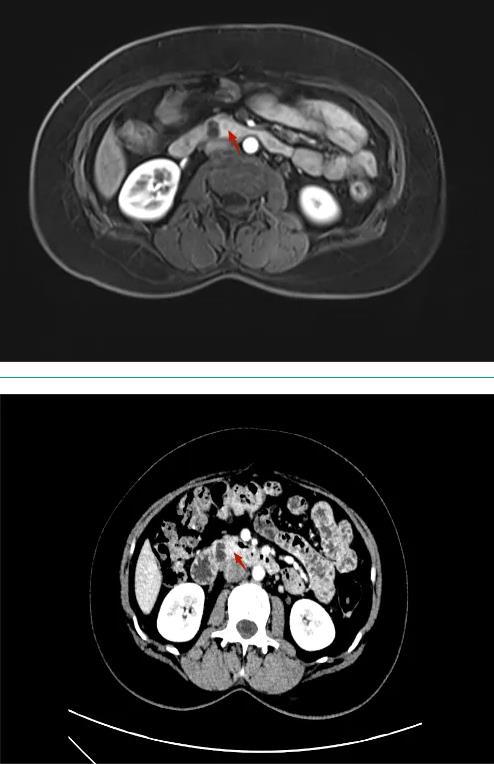

患者,男性,67岁,以“间断性腹痛6年,加重伴黑便4天”入院,腹部CT及MRI提示胰头钩突占位,考虑神经内分泌肿瘤可能性大,肝S2段占位,考虑肿瘤性病变;EUS提示胰腺钩突部可见一4.3*3.3cm大小实性占位,肝S2段可见2.1*1.7大小实性占位。行EUS-FNB病理结果回归提示神经内分泌瘤(NET G2)。